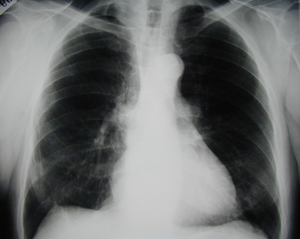

Figure 1

Postero-anterior chest X-ray that reveals the existence of a shadow in the right lung, of a male patient heavy smoker.